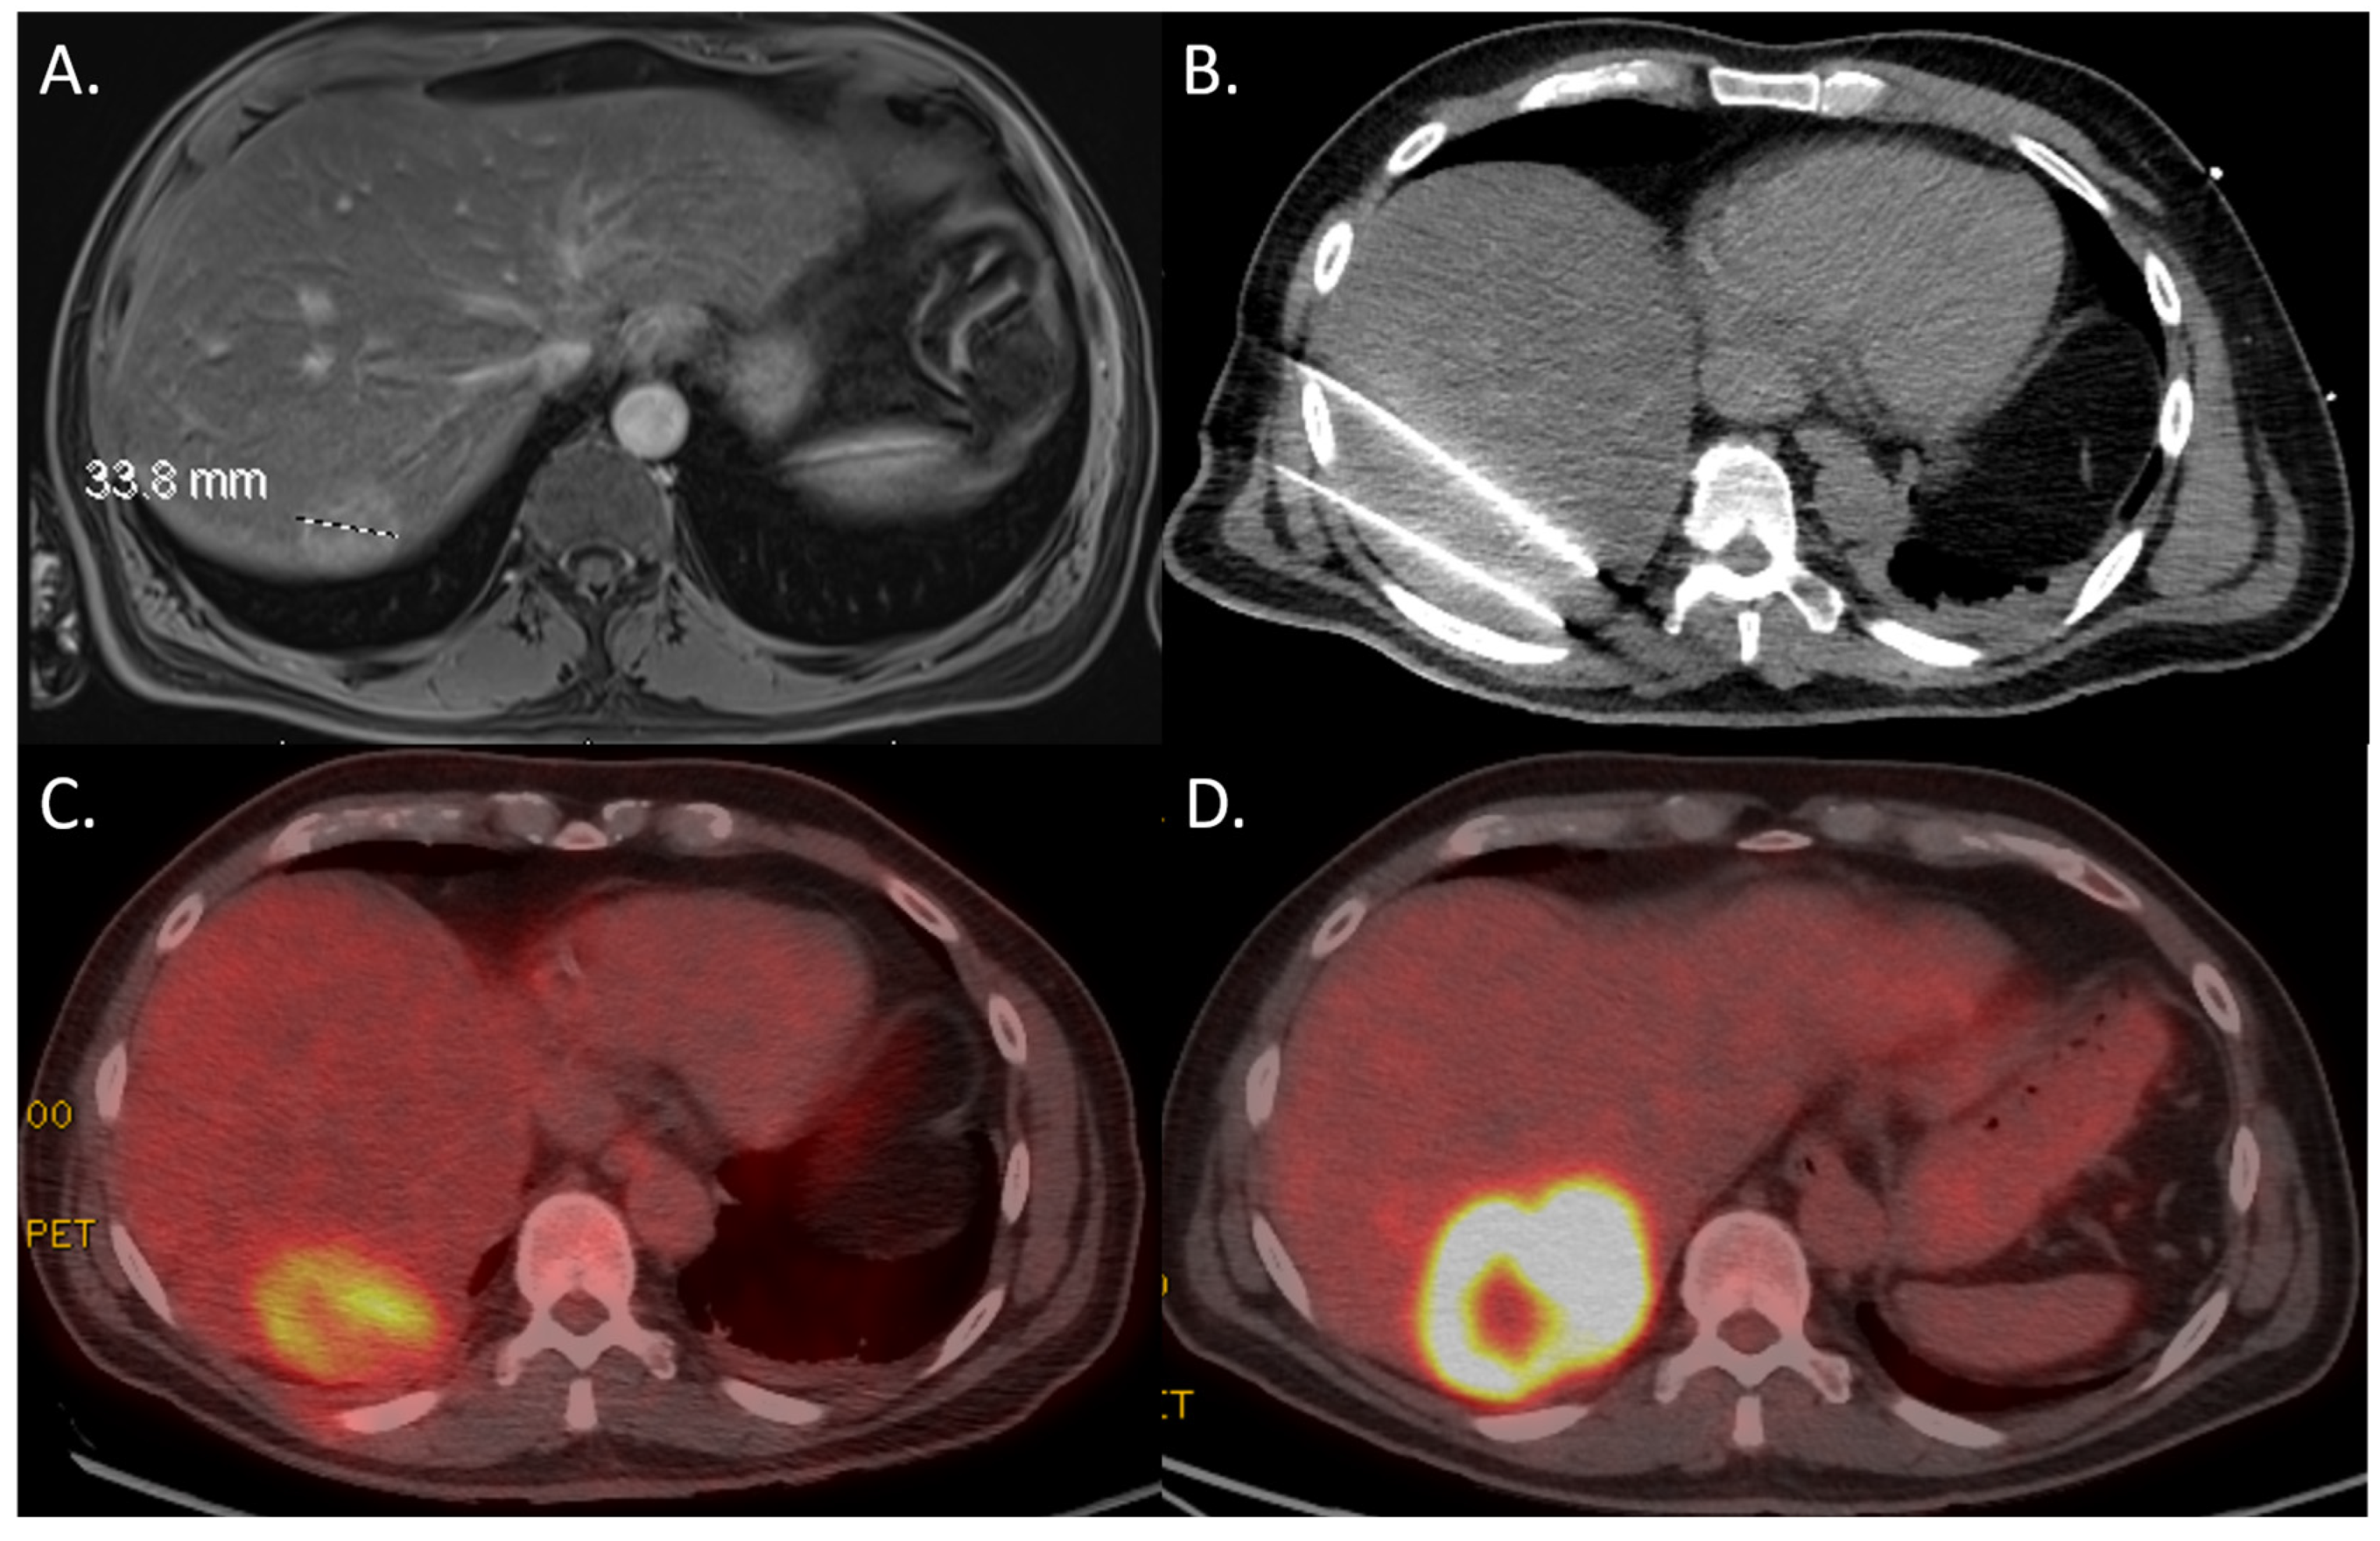

3.4. Multivariable Analysis